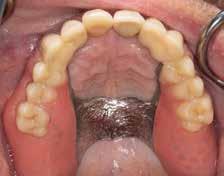

Abb. 7: Intraorale Ansicht Oberkiefer nach Beschliff

Modellgussprothesen für den Oberkiefer und den Unterkiefer hatte, wurden diese herangezogen und als Immediatersatz erweitert sowie unterfüttert. Während der Planung entschied sich das behandelnde Ärzt:innen-Team sowohl im Ober- als auch Unterkiefer für eine teleskopierende Metallgerüstprothese. Zahn 11 wurde mittels Adhäsivtechnik aufgebaut und darüber hinaus für Zahn 21 eine Einzelzahnzirkonkrone geplant. Um eine adäquate Retention der Kronen gewährleisten zu können, wurden an fünf Zähnen gegossene Stiftaufbauten eingegliedert (Abb. 6 u. 7).